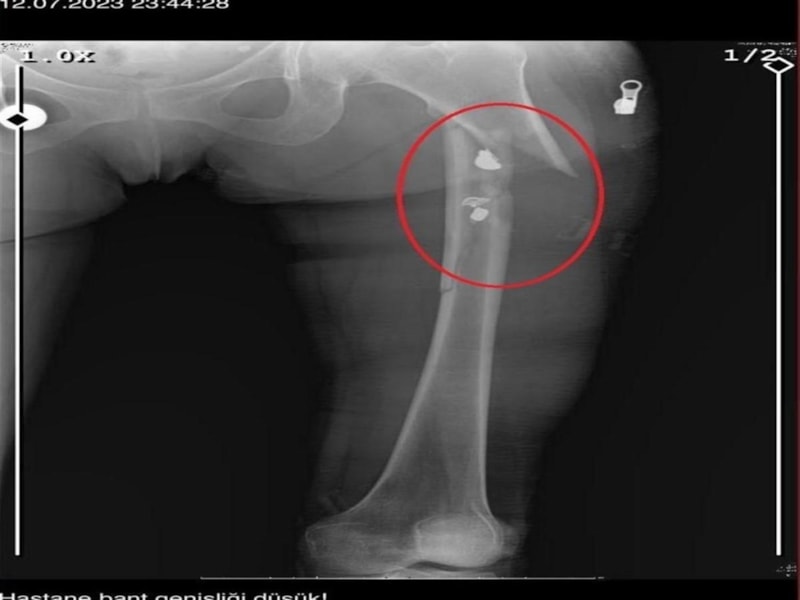

İlyas Sarıkaya, sevgilisi Fatma O.'yu da 8 kurşunla vurup, yaraladı. Arkadaşı Özaslan'ın cesedini önce çarşafa sonra da streç filme sarıp bantlayan Sarıkaya, eczaneden aldığı sargı bezi ve ilaçlarla pansumanını yaptığı sevgilisine yaralı haldeyken 21 gün boyunca cinsel saldırıda bulundu.

Eve giden ekipler, ağır yaralı haldeki Fatma O. ve kokmaya başlayan cesetle karşılaştı.